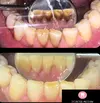

Tooth Decay

Gum Bleeding

Dental and Gum Diseases